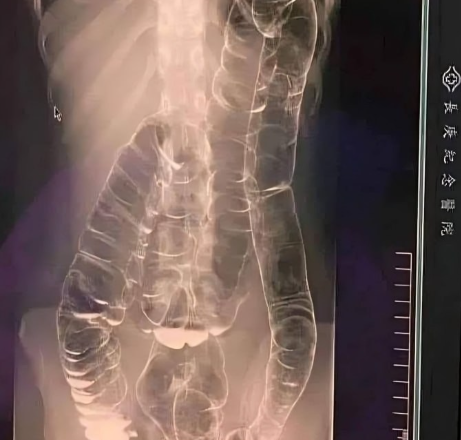

Wstrząsające zdjęcie rentgenowskie pacjenta z ciężkim zaparciem

Młoda kobieta, która od lat cierpiała na chroniczne zaparcia, doświadczyła pogorszenia stanu. Nie wypróżniała się przez ponad dwa tygodnie, co powodowało u niej silny dyskomfort i niepokój. W końcu zgłosiła się po pomoc lekarską, a wyniki były alarmujące.

- Jelito grube rozszerza się znacznie ponad swoje normalne rozmiary, próbując zatrzymać nadmiar odpadów.

- Na zdjęciu rentgenowskim widoczne jest rozciągnięcie jelita grubego w kierunku klatki piersiowej, w pobliżu serca.

- Silne wzdęcia powodują spłaszczenie naturalnych fałdów jelita grubego, co utrudnia jego prawidłowe funkcjonowanie.